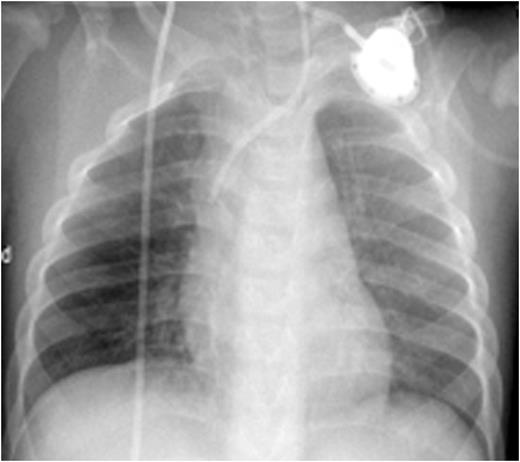

CXR before administration of plasminogen showed atelectasis of the left lung and of the right lower lobe (left panel). Six weeks after initiation of regulalar plasminogen substitution ventilation in both lungs had improved significantly (right panel)